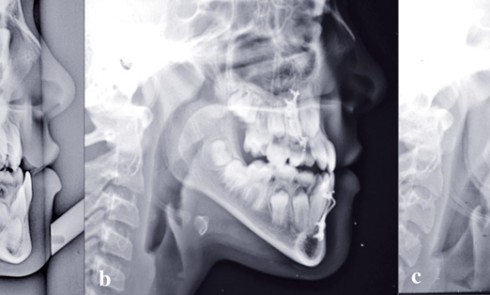

Article réservé à nos abonnés Chirurgie orthognathique guidée

Filière numérique, protocole Phase initiale d’acquisition et de traitement des données natives (segmentation)Elle est enclenchée une fois terminée la préparation...